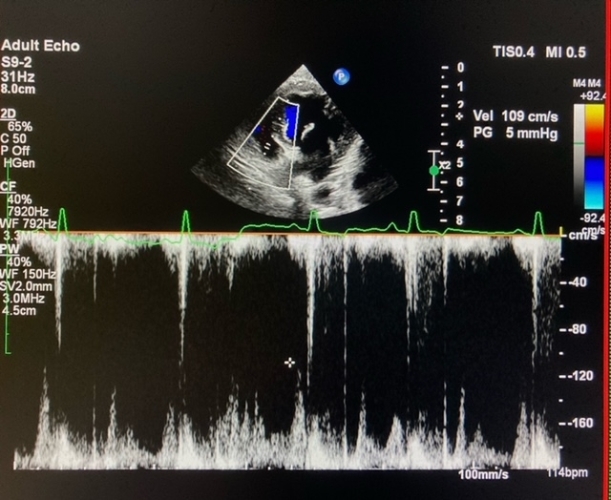

心臟超聲波

除了一般心臟檢查之外,我們也經常使用心臟超聲波告訴我們更多關於心臟的結構,心室尺寸,泵送能力,瓣膜功能,血流量等。它現在已經成為評估患者的心臟問題嚴重程度的常規診斷程序, 評估是否需要特定的心臟藥物。